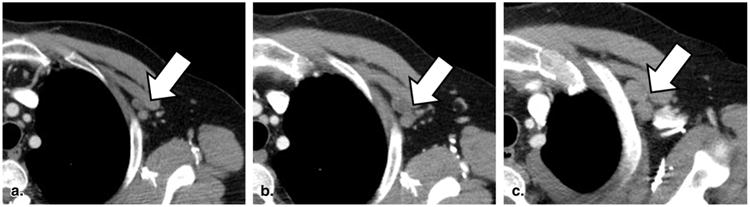

Figure 6.

Equivocal progressive disease for a nontarget lesion (60-year-old female with non-small cell lung cancer). Contrast-enhanced computed tomography of the chest reveals a cluster of left subpectoral lymph nodes that are slowly growing over time (a–c). According to Response Evaluation Criteria in Solid Tumors, an assignment of progressive disease for these nodes must be considered with reference to overall disease burden on the rest of the scan.